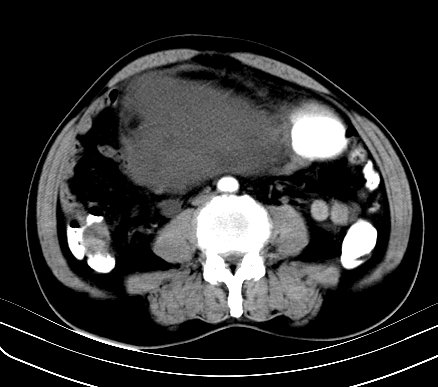

标题: CT19729B:男,74岁,因腿疼就诊,查体触腹部肿物,

增强扫描

动脉期

【ct表现】

1、肿块巨大,往往位于腹膜后,长大后才引起症状而就诊;那么位于腹膜后的肿瘤80%为恶性肿瘤。

2、实性肿瘤,增强扫描轻度不均强化,实性肿瘤一般不是好东西。

3、肿瘤边缘似见少许脂肪样密度。

4、腹膜后未见肿大淋巴结,但肿瘤于临近的肠管及组织接触紧密。

【诊断】

腹部占位,考虑位于腹膜后的恶性肿瘤,脂肪肉瘤(实体型)可能性大。

应该是腹腔病变,病灶较大,内可见脂肪密度影,边界较清,有钻孔样改变,表皮强化,考虑畸胎瘤(皮样囊肿)可能性大.

囊性肿物较大,定位有一定困难,考虑腹腔内肠源性肿瘤或腹膜后间隙囊性肿瘤.性质待定.

术后病理结果:腹膜后脂肪肉瘤。